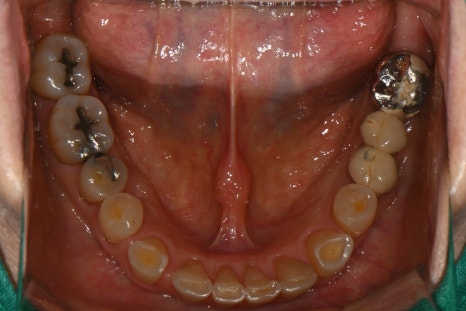

어금니 임플란트 식립 및 보철물 완성 후 구강 내 사진

어금니 부위에 임플란트를 식립한 후, 크라운까지 셋팅이 완료된 모습입니다. 자연치와 조화로운 색상과 형태로 기능과 심미성을 동시에 회복했습니다.

"자연치처럼 조화롭고 심미적으로 완성된 앞니 크라운과 기능을 회복한 임플란트 보철 모습입니다."